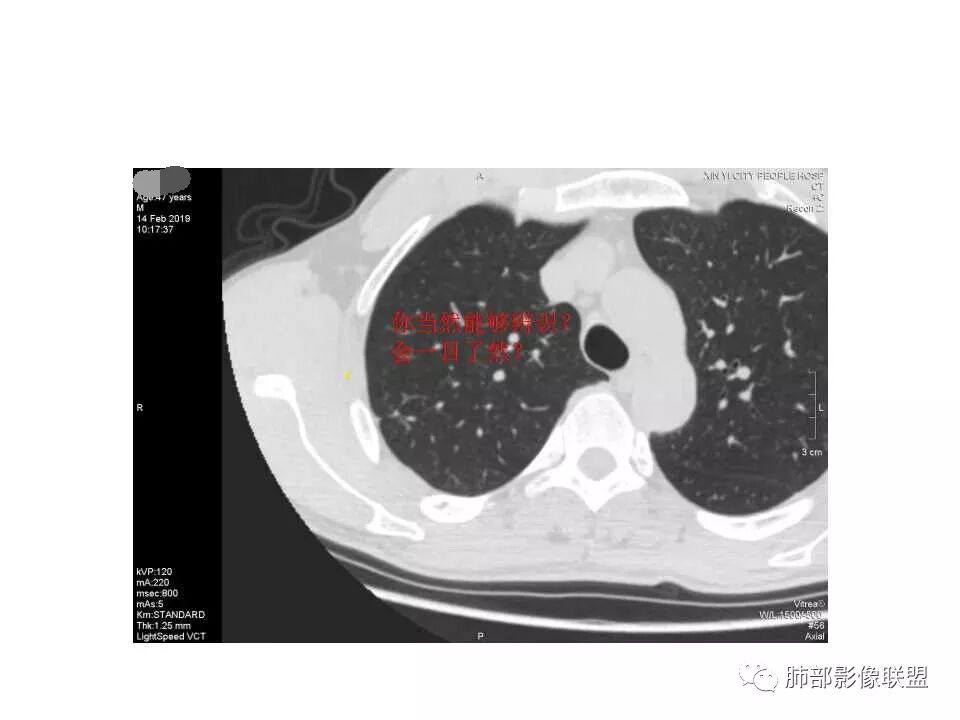

南边:问一个问题:支气管在这里堵了吗

Shelia:堵了,而且支气管壁增厚了。

Coke with ice:我认为堵了,不倾向于肿瘤的堵塞。对于这个病例来说,结核的爬行和肿瘤的堵塞鉴别点不清晰。

南边:这是支气管吗?

张立:是

南边:

远端有支气管显示,提示支气管局部没有堵塞,这个近端的看起来堵塞的支气管可能是假象。

这是我首先把它定在炎性,附近有一些小卫星灶,我还是倾向结核放在前面,待排恶性肿瘤。刚才有老师考虑隐球,这个就不太支持,因为它的长轴是沿支气管过来的,这明显就不是隐球特点。附近有一些小卫星灶,我还是倾向一个结核的可能性大。